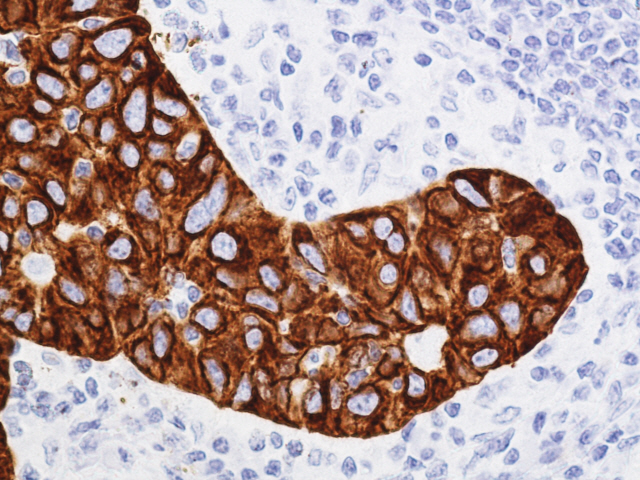

7. Pattern of staining

8. Intensity of staining